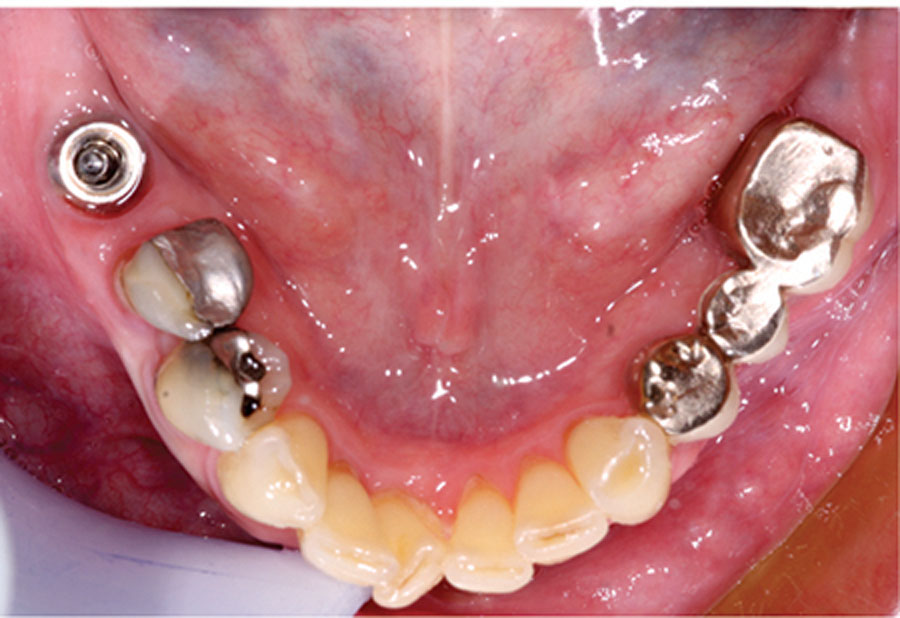

Reducing Extraction-to-Final Restoration (EFR) Time Utilizing a 5-in-1 Technique

Abstract Although immediate implant placement and provisionalization are now considered the standard of care and the preferred patient option for transitioning from edentulism or unrestorable teeth to implant rehabilitation, several clinical factors and patient characteristics can contraindicate this approach. As a result, it is still frequently necessary for clinicians to undertake—and for patients to endure—the … Read more